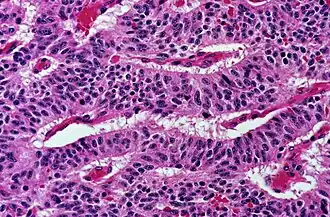

A typical carcinoid tumor of the lung showing a trabecular pattern of elongated groups of cells.